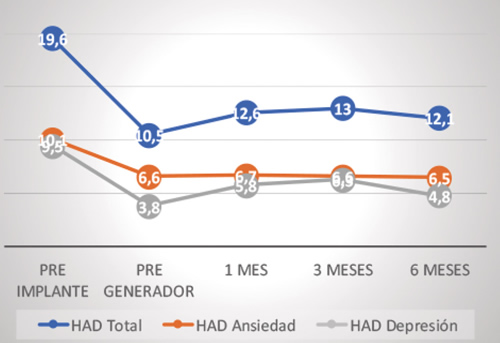

Hubo una disminución significativa en los niveles de ansiedad y depresión medida mediante las escalas de ansiedad y depresión hospitalarias (HAD), respecto a la basal (19,4 ± 7,5): 10,5 ± 6,8 (p = 0,009) a 2 semanas, 12,6 ± 8,3 (p = 0,036) a 1 mes, 13 ± 6,9 (p = 0,43) a 3 meses y 12,1 ± 7,4 (p = 0,042) a 6 meses (Figura 4).

Fig. 4. Niveles de ansiedad y depresión según escala HAD

En la subescala de ansiedad, respecto al valor basal (9,9 ± 4,5), la disminución fue significativa a las 2 semanas (6,6 ± 4,7; p = 0,048), y mostró una tendencia a la significación en el resto de evaluaciones: 6,8 ± 4,4 (p = 0,064) a 1 mes, 6,6 ± 3 (p = 0,056) a 3 meses y 6,5 ± 3,9 (p = 0,061) a 6 meses (Figura 4).

En la subescala de depresión: respecto al valor basal (9,5 ± 4,4), la disminución fue significativa a las 2 semanas (3,9 ± 3,3; p = 0,004) y a los 6 meses (4,9 ± 4,4; p = 0,030), y mostró una tendencia a la significación en las evaluaciones a 1 mes (5,9 ± 4,5; p = 0,064) y a 3 meses (6,4 ± 4,3; p = 0,099) (Figura 4).

Los cambios en el humor o los niveles de ansiedad sufrieron una mejoría similar, patente y mantenida en el tiempo. El estudio Accurate (12) pone de manifiesto una diferencia estadísticamente significativa en los parámetros del Short-form-36 en humor, tensión y depresión a favor de los pacientes sometidos a EGRD con respecto a los portadores de dispositivos de ECP, también con estabilidad en la mejoría en los diferentes controles hasta los 12 meses de seguimiento.